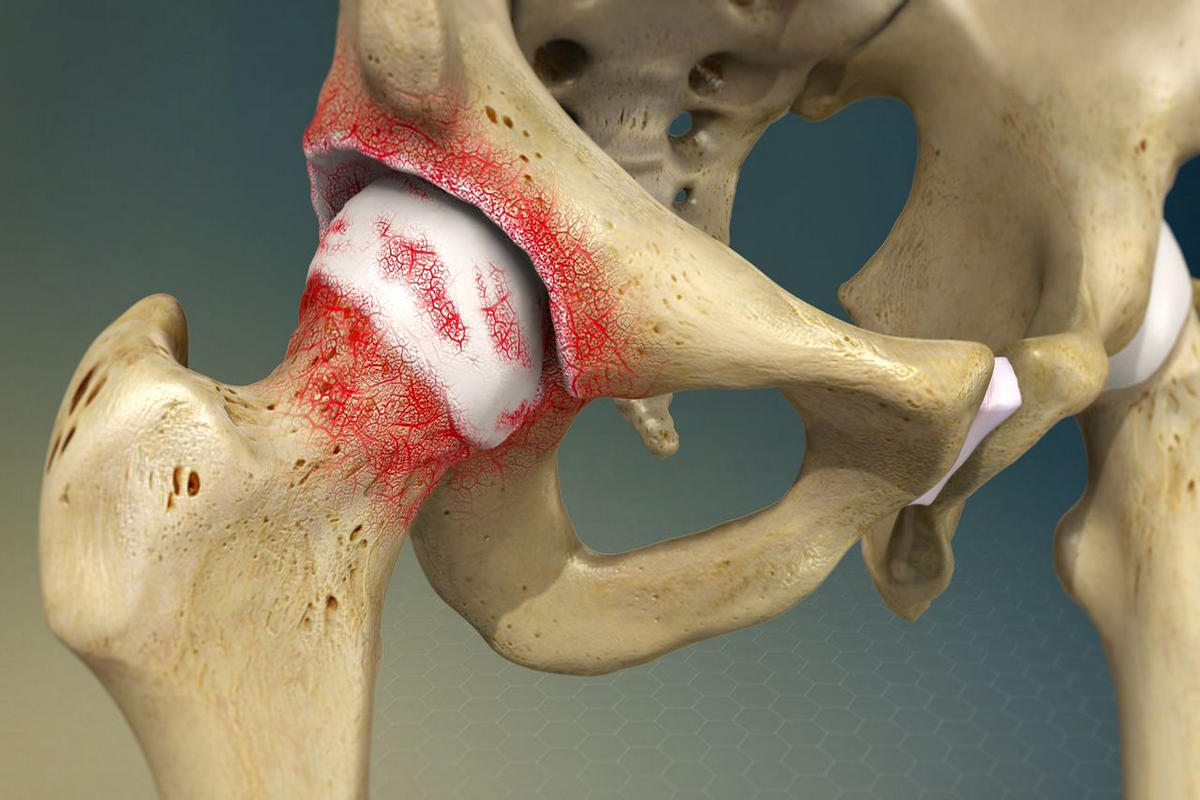

Η άρθρωση του ισχίου αποτελεί σφαιροειδή άρθρωση μεταξύ της μηριαίας κεφαλής και της κοτύλης. Ο αρθρικός χόνδρος καλύπτει τις επιφάνειες αυτές και επιτρέπει ομαλή και ανώδυνη κίνηση.

Στην αρθρίτιδα ισχίου, ο χόνδρος φθείρεται ή καταστρέφεται, με αποτέλεσμα τριβή «οστού με οστό», φλεγμονή και προοδευτική παραμόρφωση της άρθρωσης.